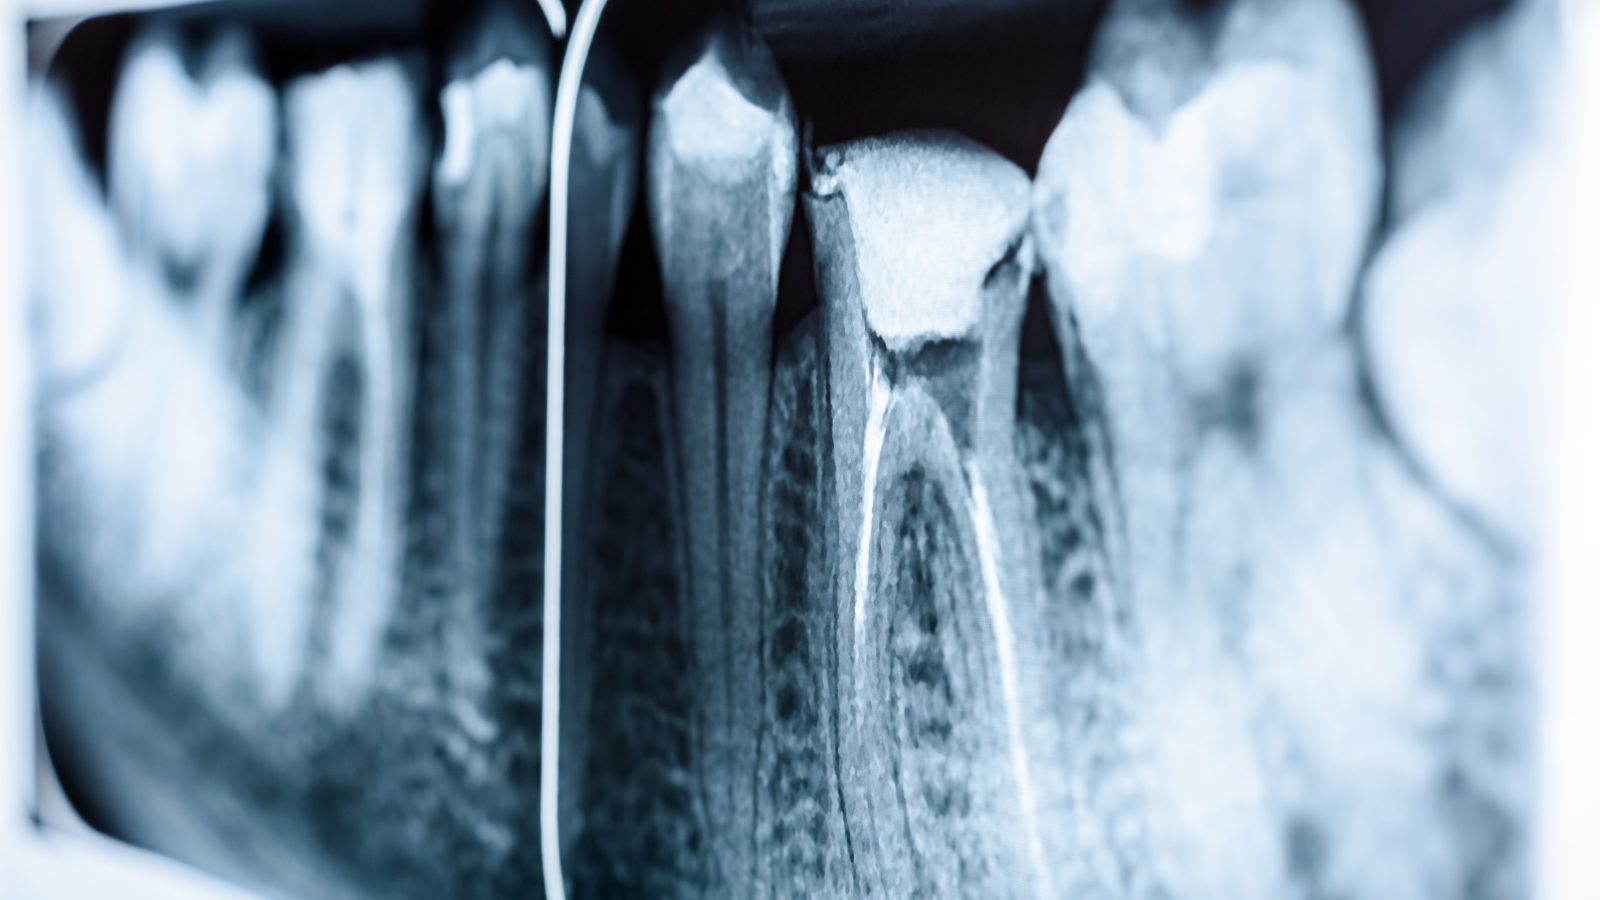

デンタルレントゲンは、数本の歯を詳細に撮影する小さなレントゲンで、1枚あたり約50点(約500円)、3割負担で約150円程度です。

虫歯の深さや根の治療が必要かどうかを確認する際に使用され、治療の精度を高めるために重要な検査です。

レントゲンを撮影することで、虫歯がどこまで進行しているか、神経まで達しているかどうかを確認できます。

浅い虫歯であれば、削って詰める簡単な治療で済みますが、神経まで達している場合は根管治療(神経を取る治療)が必要になります。

根管治療には複数回の通院が必要で、費用も増えるため、レントゲンで正確に診断することが重要です。